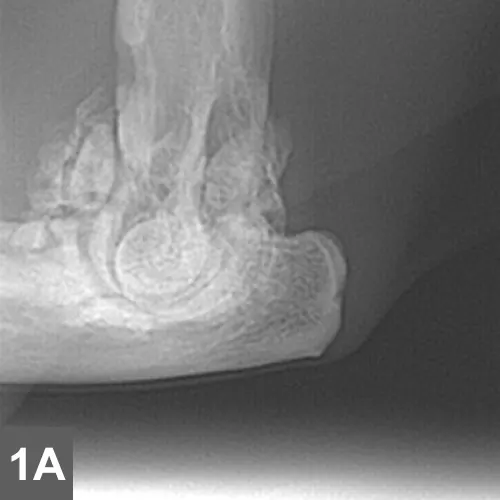

For conclusive proof of osteoarthritis, look for radiographic signs supportive of the loss of articular cartilage, osteophyte formation, bone remodeling, and inflammation along with cytology of joint fluid showing increased inflammatory cell counts and protein levels and decreased viscosity of fluid (see Laboratory Findings/Imaging for further discussion). Spondylosis deformans is diagnosed radiographically by identifying bony spurs of the fibrocartilagenous intervertebral joints of the spine (Figures 1 and 2).

A lateral radiograph of a canine elbow joint shows significant osteophyte formation and joint effusion, indicating potential osteoarthritis. The image highlights the altered bone structure and soft tissue changes associated with the condition.

• Radiographs of DJD will depict bone spurs, osteophytes, joint surface lucencies, or narrowed joint space reflecting loss of articular cartilage. There is generally no increase in volume of joint fluid associated with degenerative conditions; however, joint space may be wider than normal if severe inflammation is present.